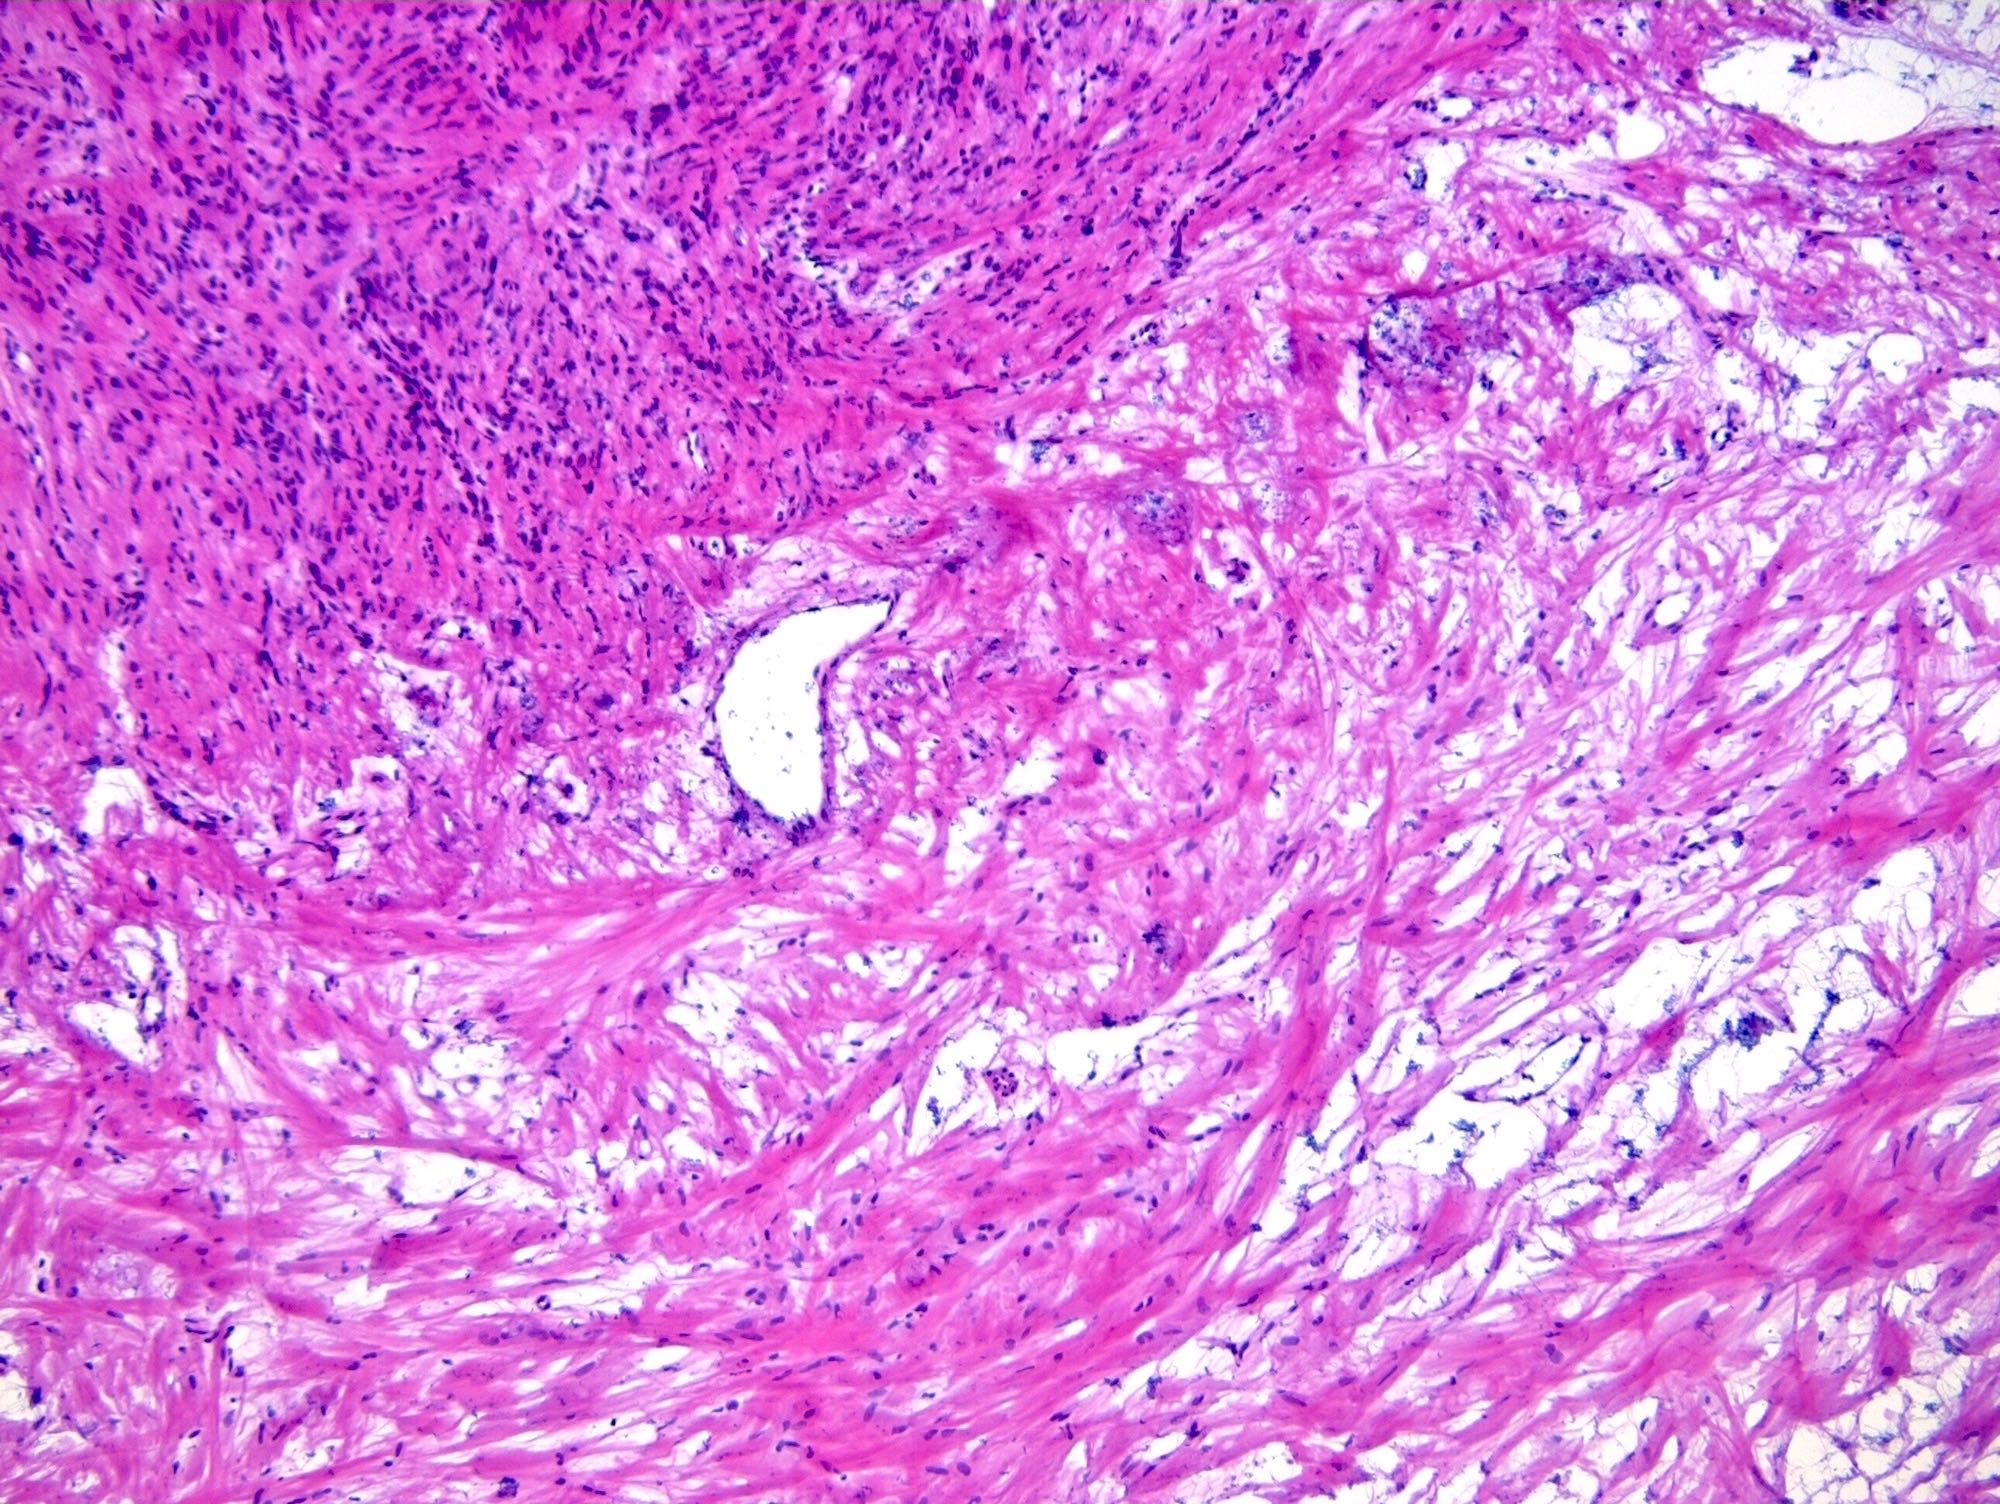

Microscopic (histologic) description

- Alternating cellular and hypocellular areas impart a pseudolobular appearance

- Hypocellular foci may be ill defined in pregnancy due to expansion of the pseudolobules by lutein cells (Int J Gynecol Pathol 2015;34:357)

- Thin, dilated and branching hemangiopericytoma-like vasculature is often conspicuous in both components

- Pseudolobules comprised of a jumbled admixture of epithelioid (lutein) and spindled cells with minimal atypia

- Epithelioid cells: round nuclei with prominent nucleoli, vesicular chromatin and clear to vacuolated cytoplasm

- Abundant eosinophilic cytoplasm often seen in pregnancy (Int J Gynecol Pathol 2015;34:357)

- Occasionally have a signet ring-like appearance

- Spindled cells: elongated nuclei with indistinct nucleoli, bland chromatin and scant eosinophilic cytoplasm

- Typically round to ovoid but may show angulation if edema is striking

- Epithelioid cells: round nuclei with prominent nucleoli, vesicular chromatin and clear to vacuolated cytoplasm

- Hypocellular areas can be edematous, collagenous (variably keloid-like) or myxoid

- Mitoses are often inconspicuous but rarely can be up to 12/10 high power fields, no atypical forms (Int J Gynecol Pathol 2016;35:549)

- Infarct type necrosis and calcification infrequent

- References: Cancer 1973;31:664, Histopathology 2022;80:360